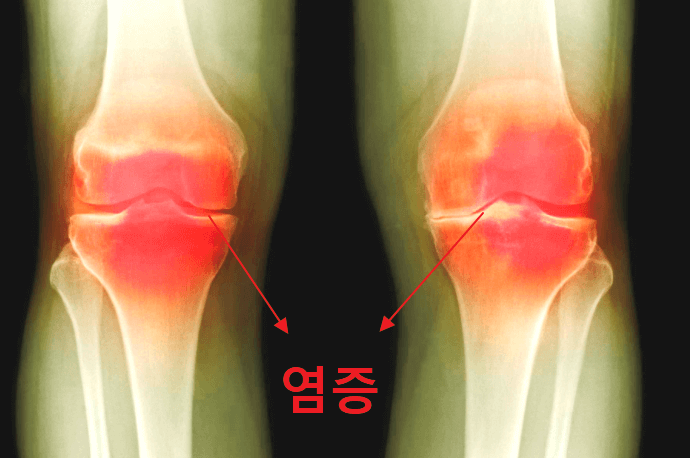

관절염이란 단어 그대로에서 알 수 있듯이 관절에 염증이 생기는 질환을 의미합니다. 관절에 염증이 생기는 이유는 대표적으로 두 가지가 있는데요. 젊은 환자의 경우 주로 격한 스포츠를 하다가 외부의 물리적인 힘에 의해 연골이 손상되고 이에 따라 염증이 발생합니다. 중년 환자의 경우 단순히 많이 사용해서 연골이 닳아 그 부위에 염증이 발생하는데요. 이를 퇴행성 관절염이라고 합니다.

연골에는 피가 흐르지 않기 때문에 한 번 손상되면 스스로 회복이 불가능합니다. 따라서 연골 손상이 아주 심한 경우라면 연골 이식술과 같은 수술적인 치료법이 필요하고 그렇지 않은 경우라면 주사 치료를 통해 무릎 연골 손상의 진행을 막아주고 무릎이 아파지는 통증을 줄여줄 수 있습니다.